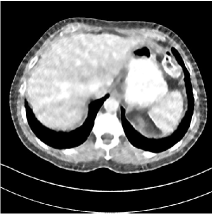

Refer to caption

Fig. 4: FBP images of test examples.